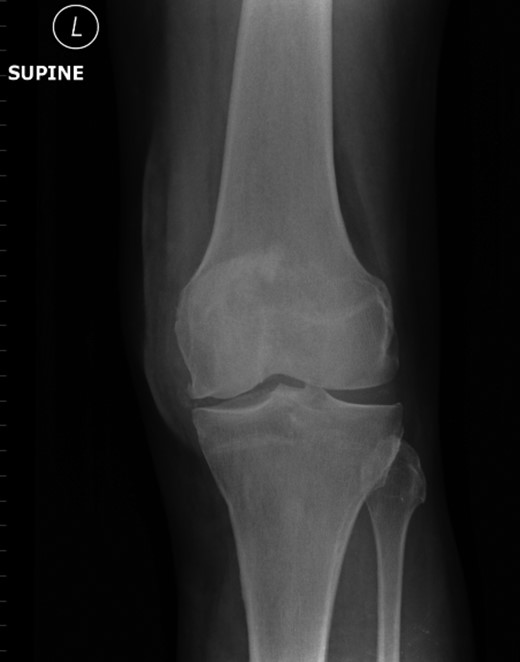

Repeat radiographs performed by his general practitioner 19 months after initial presentation (Figs 4–6) revealed a large lucency within the patella and a discontinuity in the anterior cortex of the inferior pole suggesting pathological fracture. A bone scan was arranged and demonstrated isolated abnormal tracer activity around the left patella (Fig. 7). Due to the pacemaker a computed tomography (CT) scan was performed to further characterize the lesion. This confirmed a large lucent area occupying most of the patella with multiple areas of cortical disruption along its anterior border (Fig. 8). Since the exact nature of the lesion could not be determined an ultrasound-guided biopsy was suggested but ultrasound screening revealed the lesion to be highly vascular (Fig. 9). In view of this the radiologist performed a renal ultrasound, which revealed a large mass arising from the superior pole of the left kidney. Subsequent CT of the chest, abdomen and pelvis followed demonstrating the extent of disease. There was a large (13 × 8.5 × 9 cm) mass arising from the superior pole of the left kidney (Fig. 10), the appearances of which were consistent with a primary RCC. Metastases were found in both adrenals and lungs, but no other bone metastases. Since diagnosis, the patient has had a left nephrectomy and is currently receiving radiotherapy and zolendronic acid treatment for the patella metastasis. At the time of writing this report the patient's patella lesion continues to be managed non-operatively.

The absence of associated features of systemic disease, as well as radiographic appearances in keeping with early patello-femoral osteoarthritis (OA), account for the delay in diagnosis. The initial images suggest mild degeneration but, whilst subarticular cysts are a radiographic feature of OA, the lesion shown in this case is larger than would be expected with the level of disease shown elsewhere in the joint.